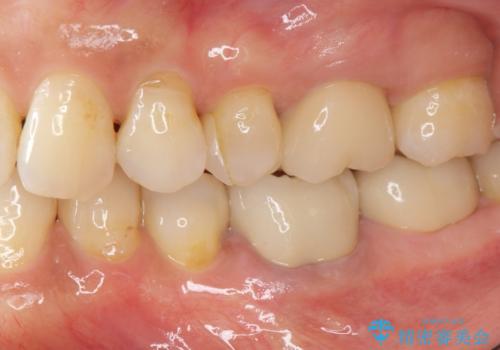

残っている歯を削らないよう、丁寧に除去したのち精密なジルコニアセラミッククラウンで再咬合構成を行っていきます。

- 31.9万円(仮歯・ジルコニアクラウン×2 セラミックインレー×1)費用は治療当時の料金となります

見た目の改善が達成できたとともに、皮膚のかゆみも明らかに減少したと喜んでいただくことができました。